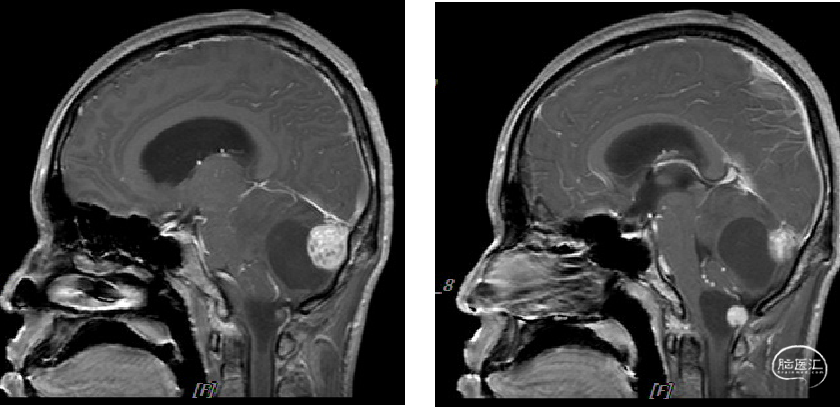

术前MRI

image.png